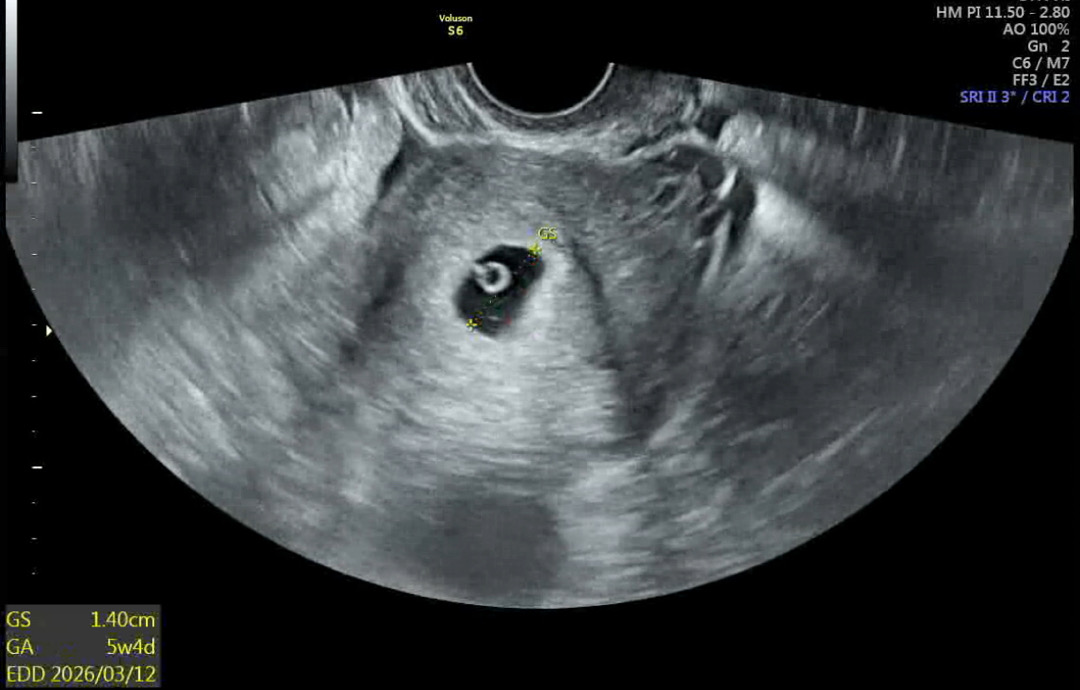

전 6주 후반에 심장소리듣고 왔어요~! 쿵쾅쿵쾅 신기하더라구요 ㅋㅋ

고사난자로 올해 4월초에 소파술 하고 다시 생긴 아가라 이번엔 정말 결과가 좋았으면 했는데 말로만 듣던 다이아 반지를 보고 왔어요 💖 다들 다이아 반지 보규 심장소리는 언제 들으러 가셨나용!? 제 다이아 반지 초음파 구경하구 가주세욤 ㅎㅇㅎ